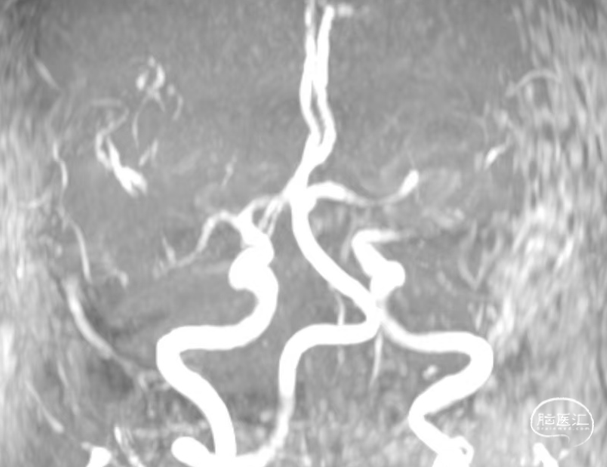

术前MRA:左侧大脑中动脉闭塞。

术前DSA造影(评估病变及代偿):Ⅰ型弓,左侧大脑中动脉闭塞;软脑膜动脉对其部分代偿,ASITN/SIR 1级。